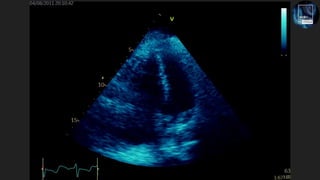

The document discusses the potential of echocardiography in managing cardiac arrest, emphasizing its non-invasive and painless nature for bedside assessments. It highlights the importance of recognizing the causes of cardiac arrest, such as hypovolaemia and tension pneumothorax, and the need for proper training of healthcare staff. Additionally, it provides resources for further learning, including social media and a dedicated website.